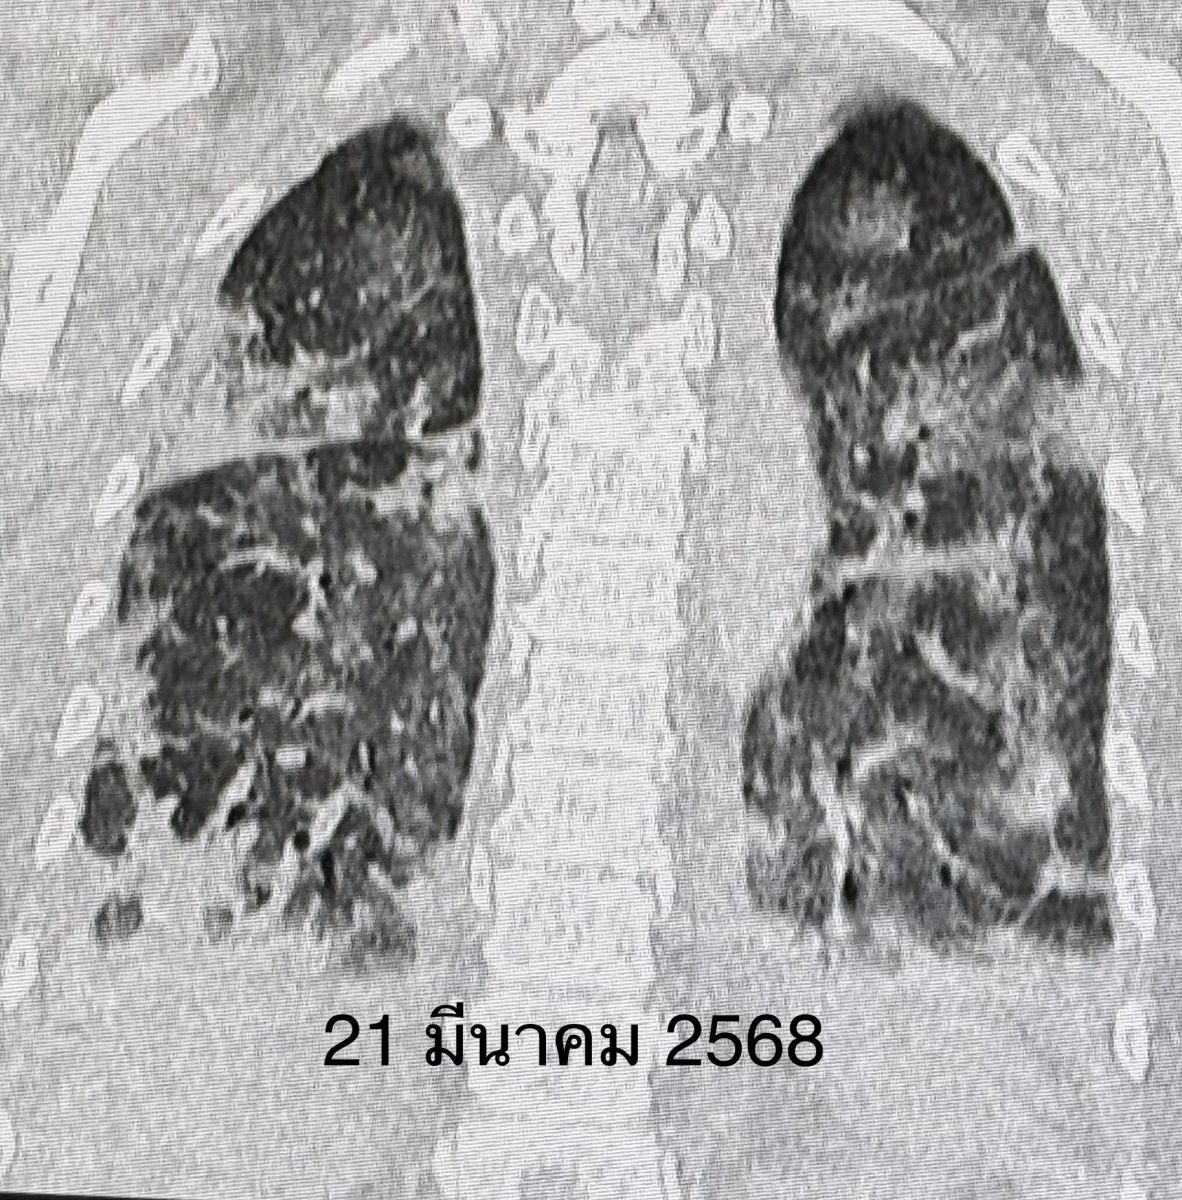

จนเริ่มเข้าโรงพยาบาลใกล้บ้านวันที่ 16 มี.ค.68 เพราะเหนื่อยมากขึ้นจนลุกขึ้นยืนไม่ได้ ไม่มีไข้ ผิวหนังปกติ กล้ามเนื้อไม่อ่อนแรง แต่ระดับออกซิเจนที่ปลายนิ้วต่ำมาก จนต้องให้ออกซิเจนชนิดอัตราการไหลสูงทางจมูก High-Flow nasal O2 cannula เจาะเลือด พบเลือดจางเล็กน้อย ค่าอักเสบในเลือด ESR และ hs-CRP สูง, ANA ปกติ ค่าโซเดียมในเลือดต่ำ เอกซเรย์ปอดและคอมพิวเตอร์ปอดพบปอดอักเสบทั้ง 2 ข้าง แยงจมูก ส่งเลือดเพาะเชื้อ ส่องกล้องเข้าไปในหลอดลม ไม่พบการติดเชื้อแบคทีเรีย ไวรัส เชื้อรา หรือวัณโรค ได้ยาปฏิชีวนะ เอกซเรย์ปอดไม่ดีขึ้น หลังรักษารพ.ใกล้บ้านมา 26 วัน ญาติขอย้ายมารักษาต่อวันที่ 11 เม.ย.68